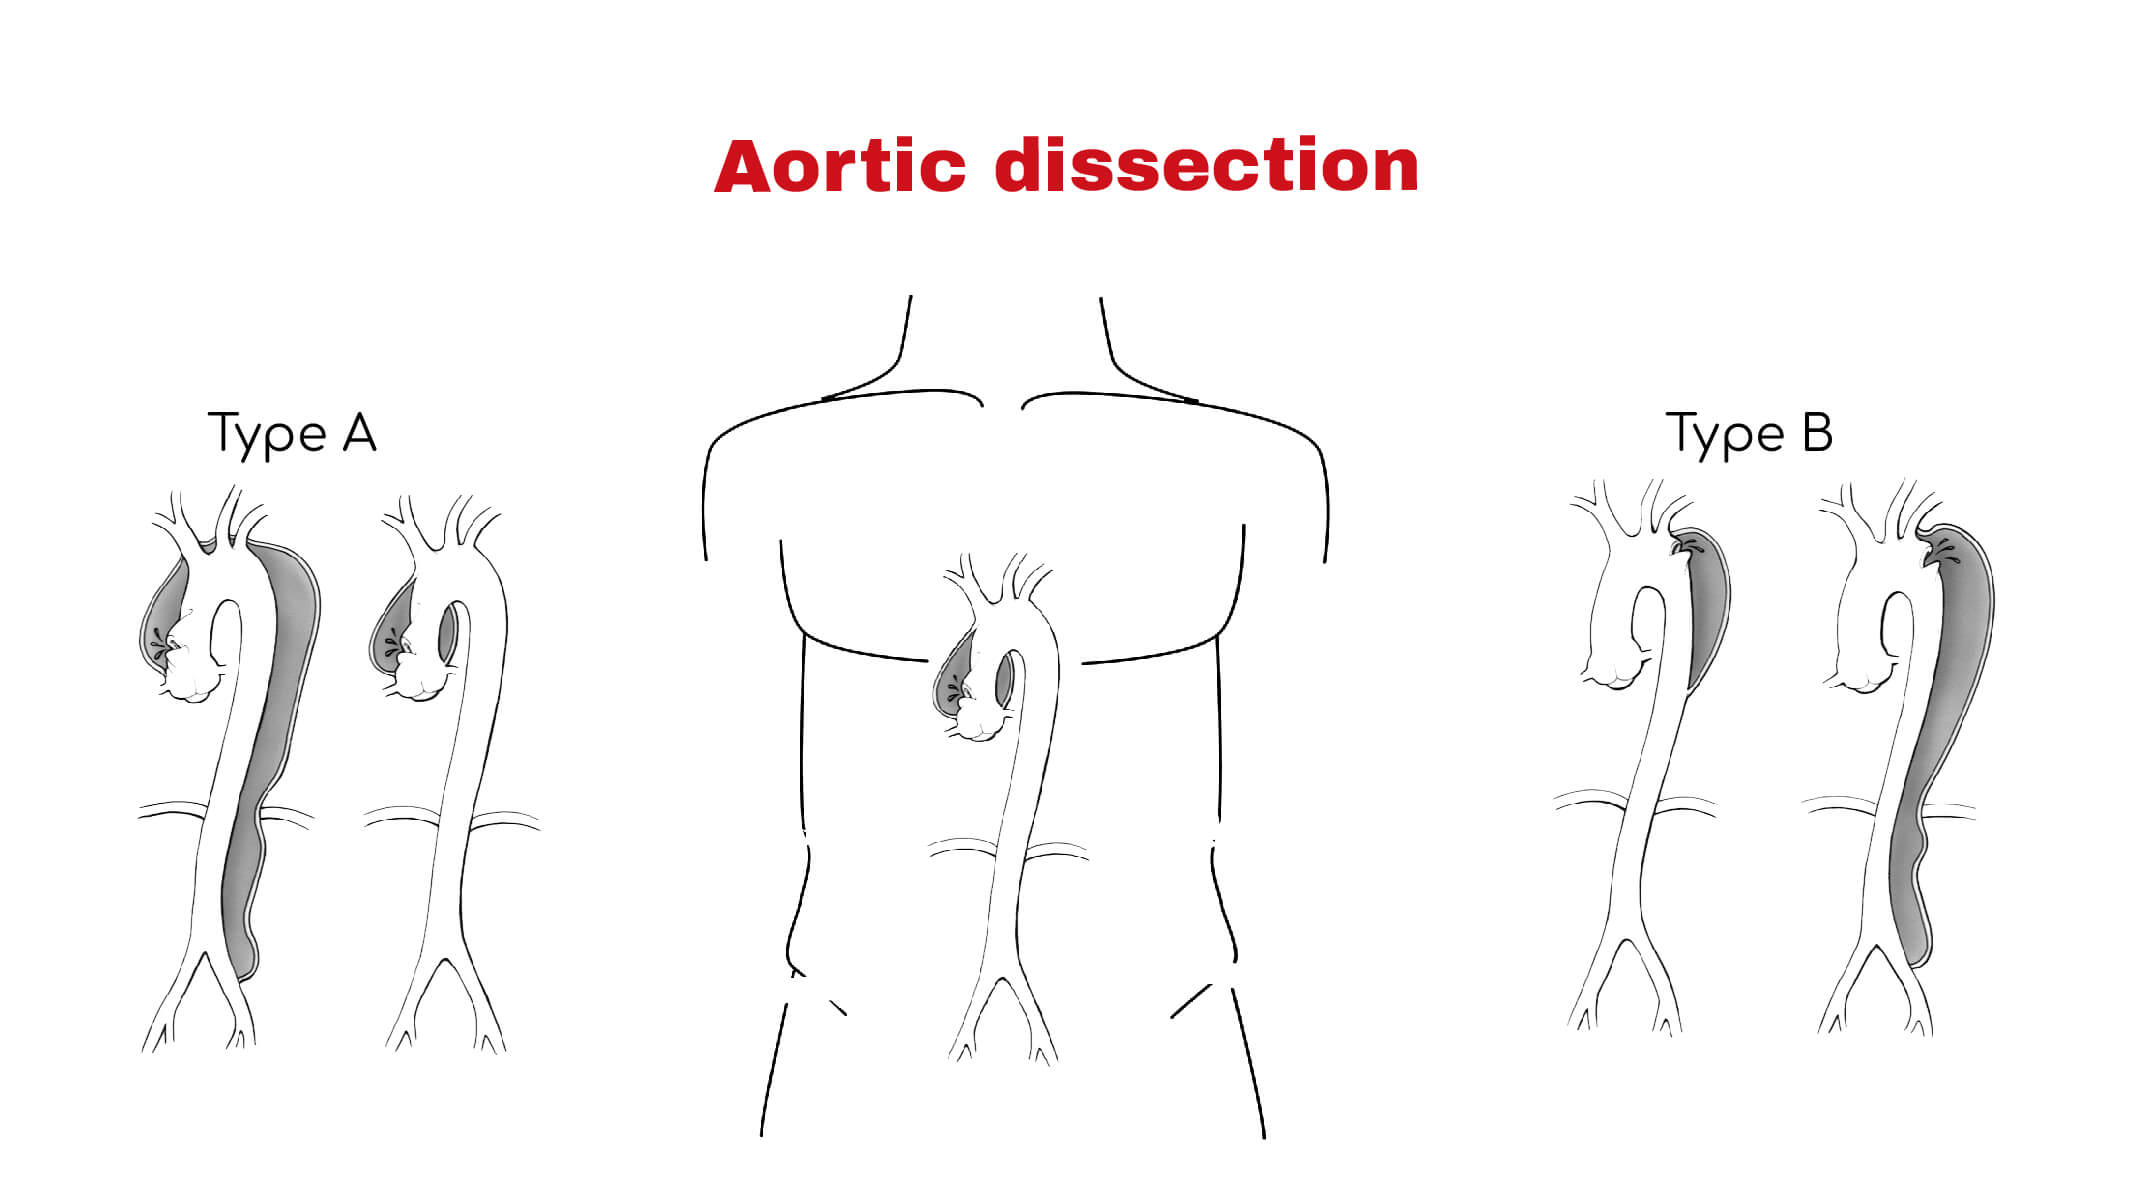

Aortic Dissection Without Chest Pain

Aortic Dissection Without Chest Pain

Aortic Dissection Chest Pain

Aortic Dissection what To Know

Aortic Dissection